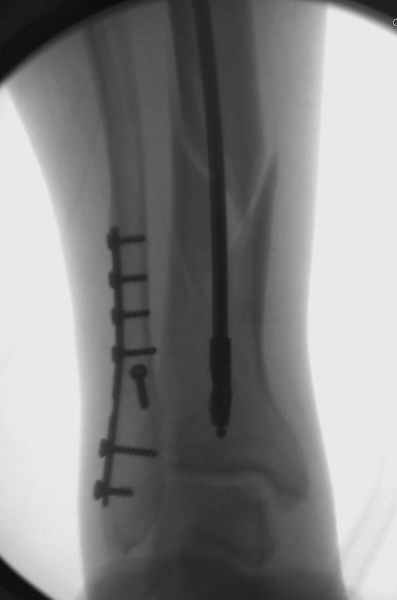

Здесь мы использовали новый Synthes Nail с дополнительными дырками, в проксимальной части 4: по две косых и поперечные (один стандартный а другой динамический), в дистальной части две поперечные, прямая и косая. Вес больного более 120 кг, нагрузку начнем через месяц.

Получилось красиво, поздравляю. Вверху можно было ограничиться одним винтом во фронтальное статическое отверстие, зачем два 45-градусных?

При такий спирали задний край tibia может быть сломан - нет ли этого в данном случае? На всякий случай можно было ввести 1-2 винта 4,5 мм спереди назад мимо гвоздя. Хотя самый дистальный блокирующий винт, возможно, зацепил этот отломок. А какой тут диаметр гвоздя и locking винтов?

DK> косая. Вес больного более 120 кг, нагрузку начнем через месяц.

Если там и правда сломан задний край, то лучше с нагрузкой подождать, даже будь больной полегче.